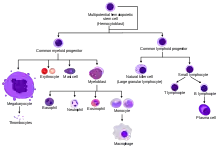

Adult Stem Cells

Adult stem cells are known as mesenchymal stem cells. Just like embryonic stem cells, adult stem cells are unspecialized cells capable of renewal and specialization, but unlike embryonic stem cells, adult stem cells are typically found in tissues surrounded by other specialized cells. This makes the stem cell only multipotent; it can only differentiate into certain cell lines as opposed to pluripotent embryonic stem cells which can differentiate into almost any cell line. The role of adult stem cells is to replenish damaged cells within tissues and organs when needed. Adult blood-forming stem cells from bone marrow have been used for transplants, and current research is underway to determine whether or not differentiation of stem cells found in the brain and heart can be controlled and used for various other forms of transplantation.

Different types of adult stem cells include the following:

- Hematopoietic stem cells: develop into bone cells, cartilage cells, fat cells

- Neural stem cells: develop into neurons, astrocytes and oligodendrocytes

- Skin stem cells: develop into epidermal stem cells and hair follicles

Adult stem cells are found in developed organisms and have the ability to divide and create another cell like itself, or create a cell more differentiated than itself.